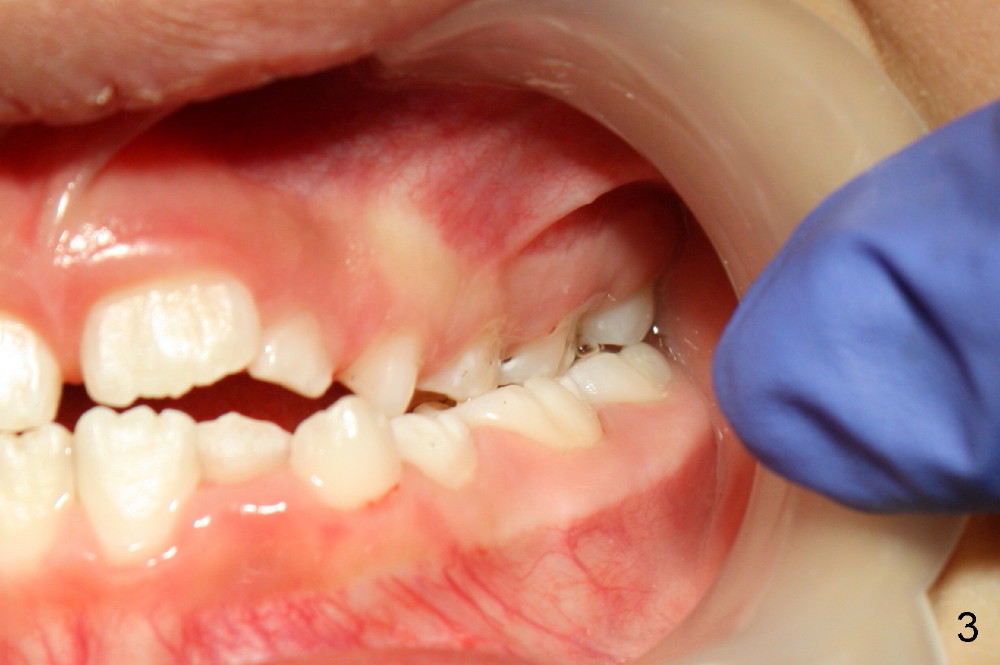

A 8-year-old girl presents malocclusion (Fig.1-3). What is the initial treatment?

Jenny: The girl has cross bite of both the anterior and posterior teeth. I think that first we need to expand her palate.